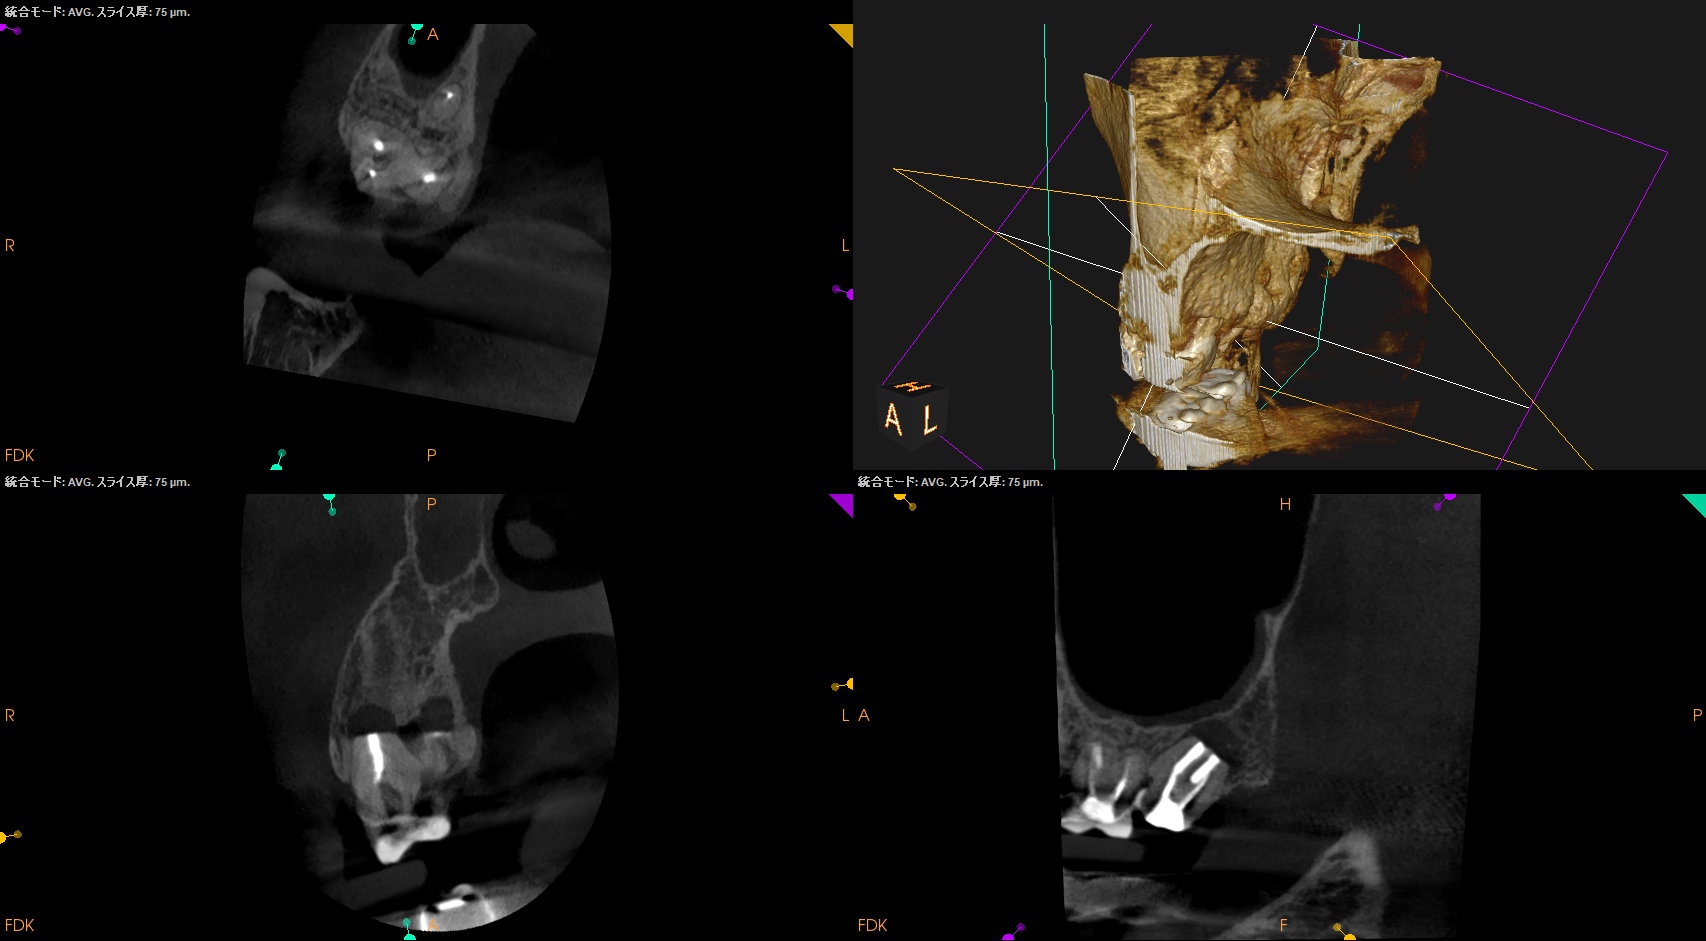

術後に口腔内PA, CBCTも撮影した。

MB

DB

P

ということで問題が客観的にないことがわかる。